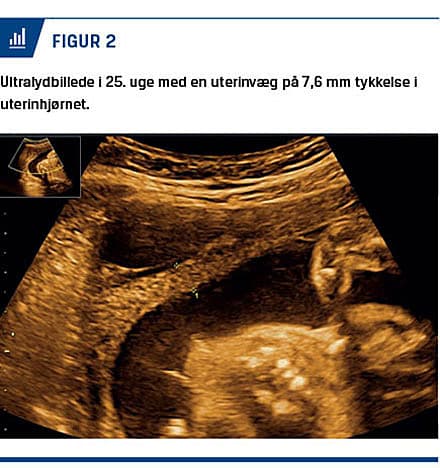

2 l frisk blod og koagler. Uterus var forstørret svarende til tiende graviditetsuge, og højre uterinhjørne var sæde for en rumperet blødende graviditet. Hjørnegraviditeten blev reseceret kileformet med diatermi, og myometriet blev lukket i to lag og pålagt fibrinogen/human trombin på det suturerede område. Peroperativ blev der givet blodtransfusion. Det postoperative forløb var ukompliceret, og der bestod en levende intrauterin graviditet ved udskrivelse. Patienten blev fulgt tæt i graviditeten med tilvækstskanninger og monitorering af uterinvægstykkelsen i det resecerede højre uterinhjørne. Der var fin fostertilvækst, men udtynding i uterinhjørnet fra 13,3 mm i 15. graviditetsuge til 3,8 mm ved GA 37 uger + 0 dage (Figur 1 og Figur 2). Man fandt vaginal fødsel kontraindiceret pga. høj risiko for uterusruptur ved veer. Man planlagde ES ved GA 38 uger + 0 dage. Ved sectio fødtes en velskabt, levende dreng. Man så følger i det resecerede højre uterinhjørne med få mm tyndt fibrinbelagt myometrium og ingen blødning fra uterinhjørnet. Det postoperative forløb var ukompliceret, og man anbefalede forløsning ved ES ved en næste graviditet.